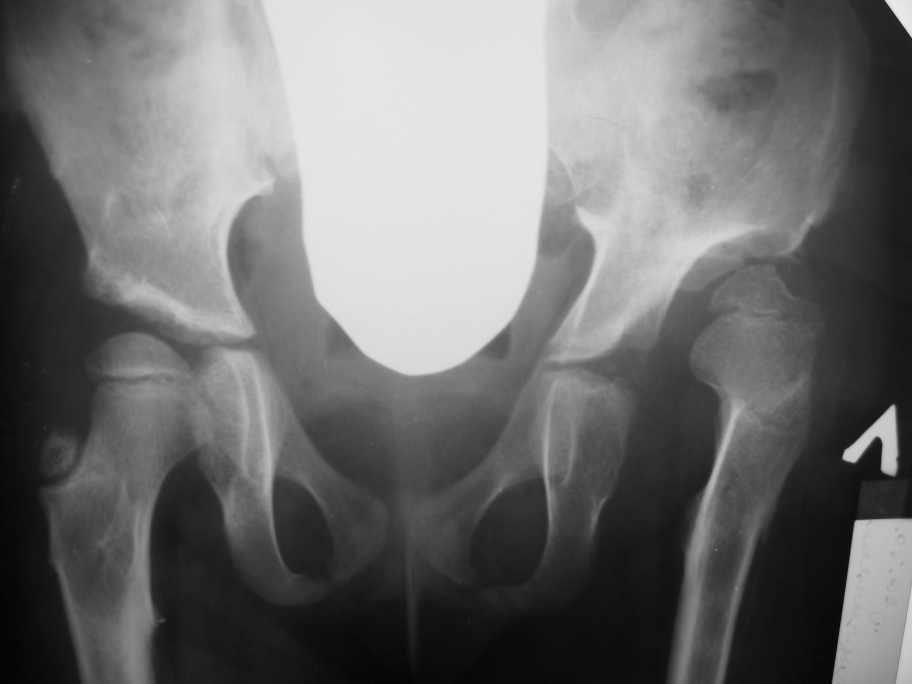

Navernoe Dega

Chto by ne byt goloslovnym posilau vam svoi sluchai gde sdelal vse chto napisal vyshe

Smotritsya parshivo konechno(pseudoacetabulum,partial AVN), no v6 let ya by popytalsya ispravit chto moghno:shortening (ne boyatsya ubrat bolshoi fragment),derotation(30 gradusov ne bolshe)+pelvic osteotomy in true acetabuluam area.Obyazatelno takghe open reduction with wide capsular exposure.